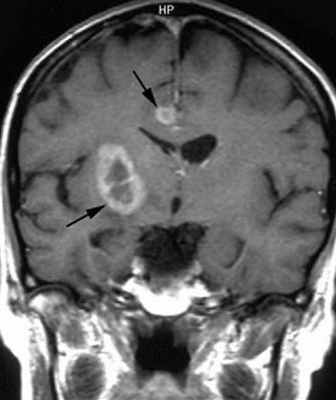

МРТ головного мозга. Туберозный склероз. Гигантоклеточная внутрижелудочковая астроцитома (стрелки). Прорастание в хвостатое ядро. Окклюзия отверстия Монро. Т2-зависимая, Т1-зависимая и Т1-зависимая с контрастированием аксиальные МРТ.